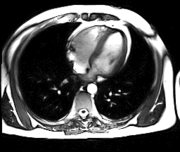

Magnetická rezonance (též MR, MRI, z anglického "magnetic resonance imaging") je zobrazovací technika používaná především ve zdravotnictví k zobrazení vnitřních orgánů lidského těla. S pomocí MRI je možné získat řezy určité oblasti těla, ty dále zpracovávat a spojovat až třeba k výslednému 3D obrazu požadovaného orgánu. Magnetická rezonance využívá velké magnetické pole a elektromagnetické vlnění s vysokou frekvencí. Nenese tedy žádná rizika způsobená zářením. Podstatou barevného odlišení jednotlivých tkání je jejich rozdílné chování při stejném vnějším působení. Jako synonymum bývá někdy používáno výrazu jaderná tomografie, od něho je ale upouštěno, protože mylně vzbuzuje dojem jakési souvislosti s jadernou energií. Více používaná zkratka MRI pochází z anglického sousloví Magnetic Resonance Imaging. Další rozvoj této metody vedl v poslední době k vývoji funkční magnetické rezonance (fMRI) a DTI = DT-MRI. Přístroj magnetické rezonance obsluhuje radiologický asistent.

Na základě naměřeného indukovaného napětí a dalších parametrů je signál pomocí složitých procesů a algoritmů převeden na škálu šedé. Právě kvůli tomu, že výsledný signál závisí na mnoha parametrech, nedá se použít žádné stupnice, která by přesně určila jednotlivé tkáně, proto se k interpretaci obrazů používá spíše rozhraní, na kterých se mění intensita signálu.

Výhodou MRI vůči ostatním zobrazovacím metodám v diagnostické radiologii je větší přesnost při zobrazení většiny orgánů, jež je důsledkem rozdílné intenzity signálu u odlišných měkkých tkání. Navíc toto zobrazení probíhá bez možného škodlivého ionisujícího záření. Některé orgány jako nervy či mozková tkáň bylo možné neinvazivně zobrazovat až právě pomocí MRI. Díky rozsahu nastavení vyšetření je možné dosáhnout rozlišení, které dalece přesahuje možnosti rentgenu či CT. Dalšího zlepšení může být ještě dosaženo podáním kontrastní látky, která pomůže odhalit přítomnost zánětů nebo nádorových tkání. Nový vývoj umožnil zkrátit časový interval získání jednoho snímku na několik milisekund. To umožnilo tzv. MRI-Fluoroskopii, při které jsou pohybující se orgány zobrazovány v reálném čase, což nachází široké uplatnění v intervenční radiologii.